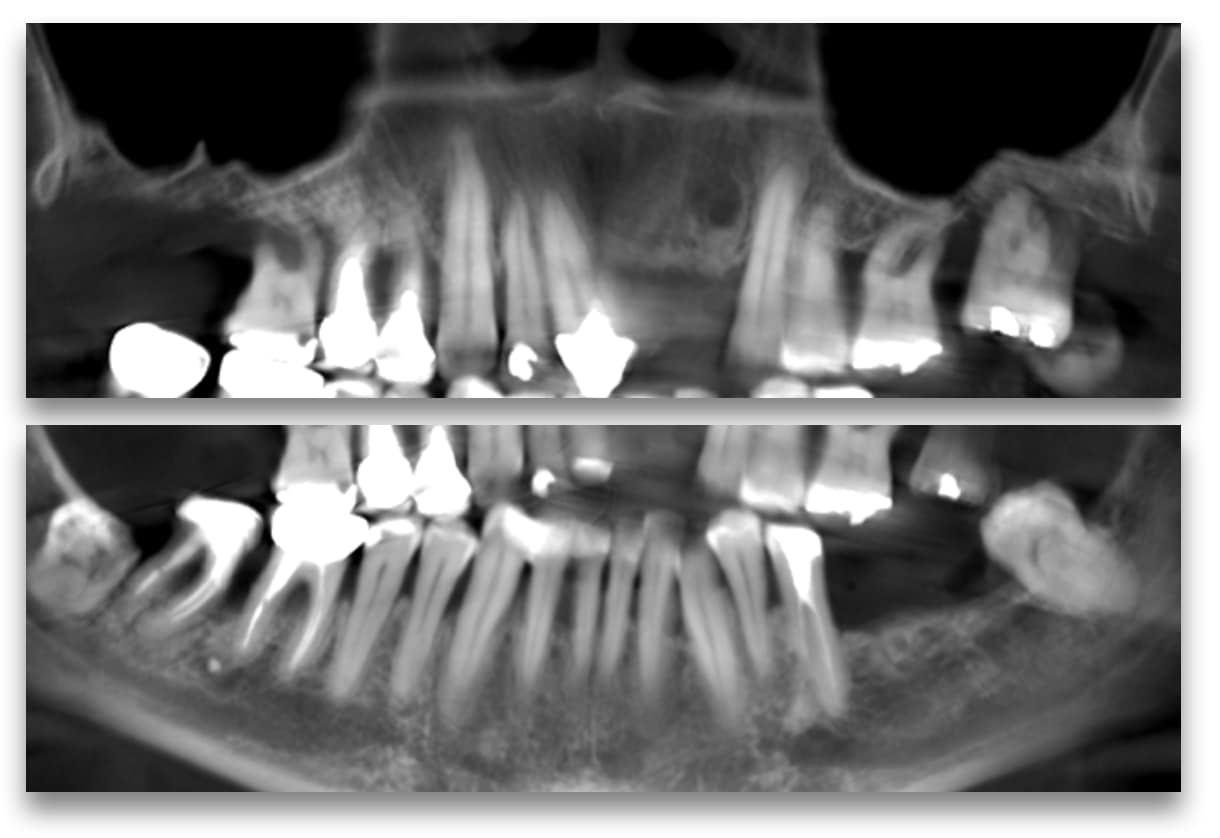

Un examen clinique approfondi et une étude cône beam montrent une situation dégradée sur beaucoup de dents et une restauration complète est envisagée au maxillaire.

Radio de contrôle à 4 mois :